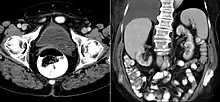

A ureterocele is a congenital abnormality found in the ureter. In this condition the distal ureter balloons at its opening into the bladder, forming a sac-like pouch. It is most often associated with a duplicated collection system, where two ureters drain their respective kidney instead of one. Simple ureterocele, where the condition involves only a single ureter, represents only twenty percent of cases.

IVU-shows Adder head appearance or Cobra head appearance. Cystoscopy-shows translucent cyst which is thin walled surrounding ureteric orifice